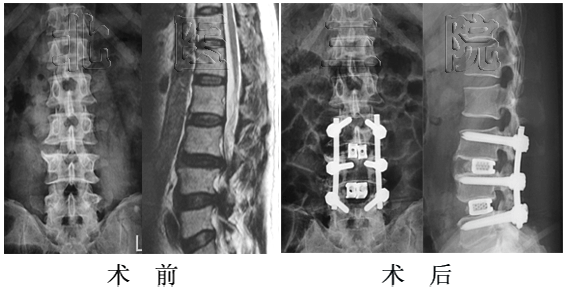

女性,65岁,成人腰椎侧凸,侧凸角度46o,行侧凸矫形固定、植骨融合,术后侧凸角度减小为5o